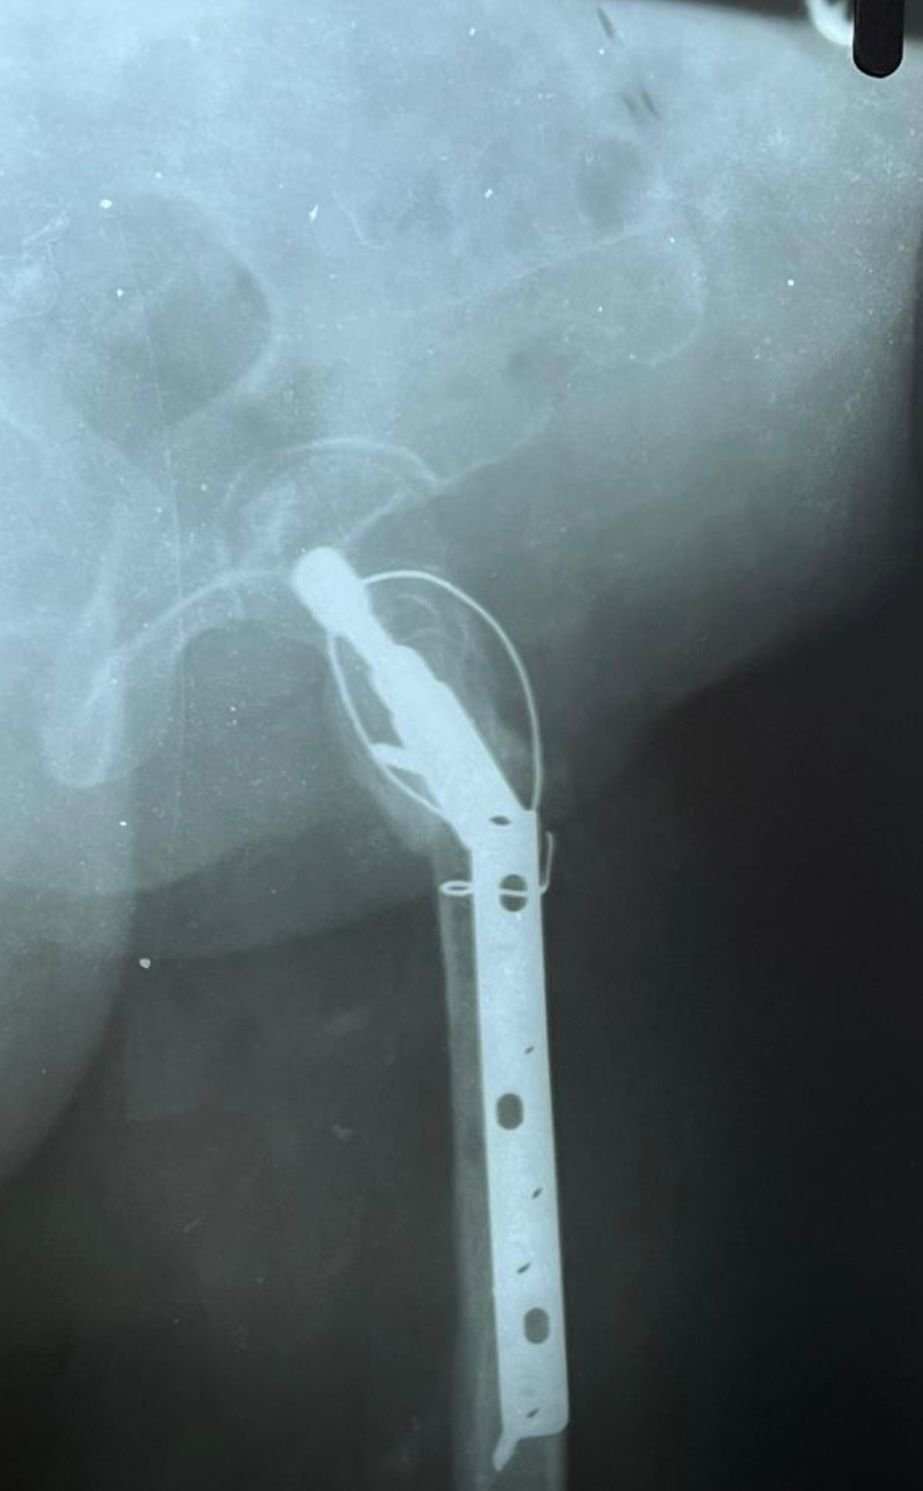

plaster & operation | Total Hip replacement case |

Non union with Broken DCS implant & revision

correction surgery